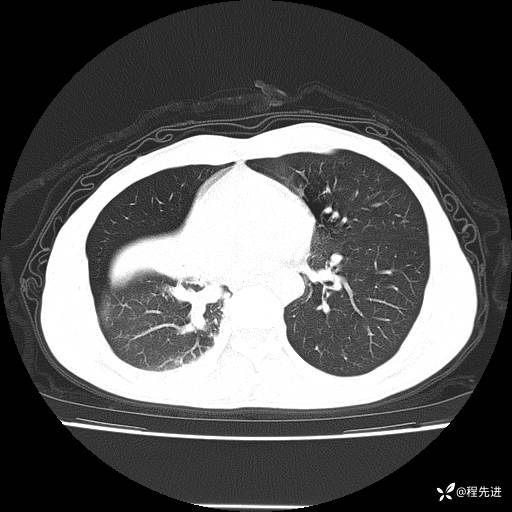

患者性别:男

患者年龄:49岁

主诉:咳嗽、胸痛1周

简要病史:1周前受凉感冒后开始出现咳嗽症状,阵发性连声咳,痰多,黄白痰,不易咳出,伴胸痛、气紧、胸闷,右侧为主,活动用力、呼吸时胸痛明显,曾在当地诊所贴敷膏药仍疼痛

体格检查:T:36.3 ℃ P:80 次/分 R:20 次/分 BP:120/88 mmHg,指脉氧饱和度97%,意识清晰,呼吸平稳,右侧第二、三肋骨压痛,可见膏药贴敷,皮肤无异常,双肺呼吸音粗,未闻及干湿性啰音。心率80次/分,节律整齐,无杂音。腹平软,全腹无压痛无反跳痛

临床诊断:社区获得性肺炎

CT平扫: